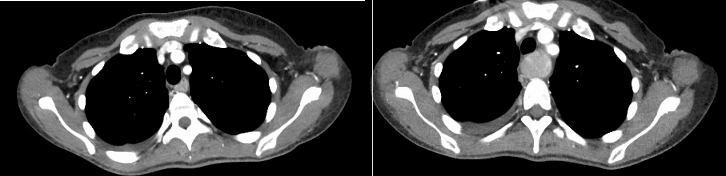

An EKG showed T wave inversions (not present on EKGs prior to this admission). A 2D echo revealed EF of 50%, normal RV and small LA from possible impingement due to an extra-cardiac mass. Repeat CT revealed a dilated esophagus that was impinging on the left atrium.

The patient underwent gastrointestinal decompression with NG tube for small bowel ileus with resolution of esophageal distension. The patient’s chest pain resolved immediately and the hoarseness and dyspnea resolved over the next 3 days.